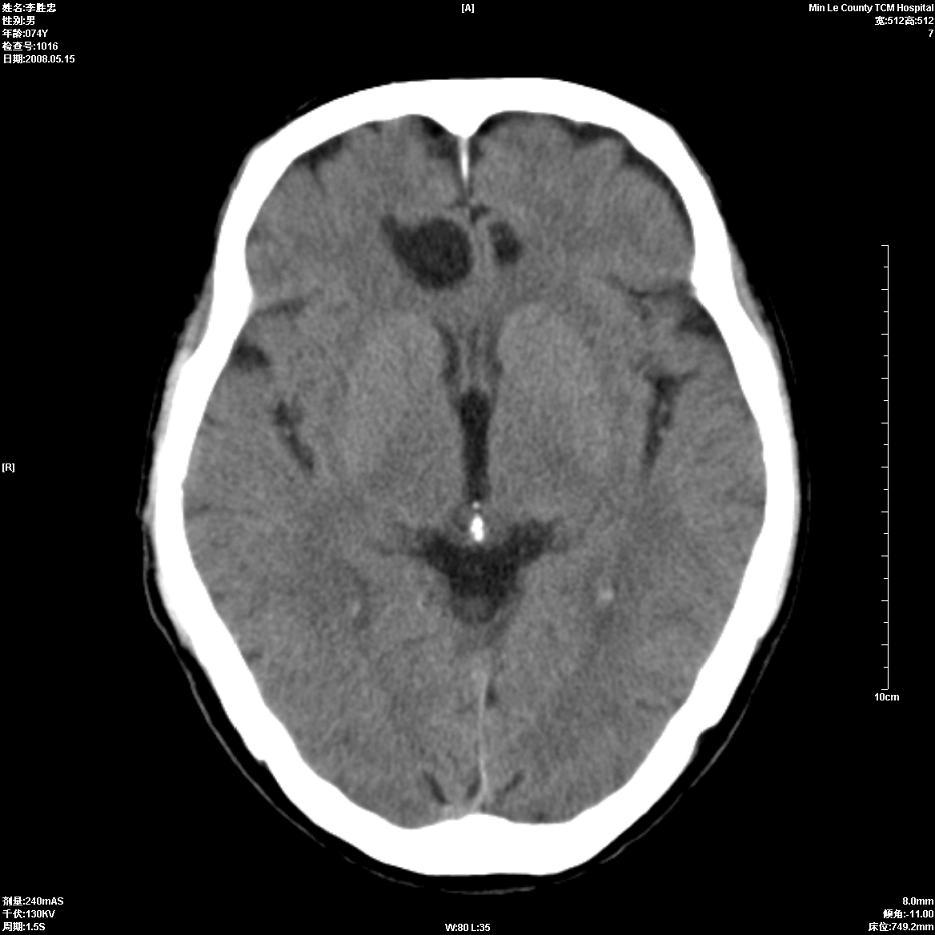

以下是引用hhcckk在2008-5-30 14:26:00的发言:[br]病灶跨中线,有占位效应,强化不明显,考虑胼胝体区低级别的星形细胞瘤可能性大,建议mr检查